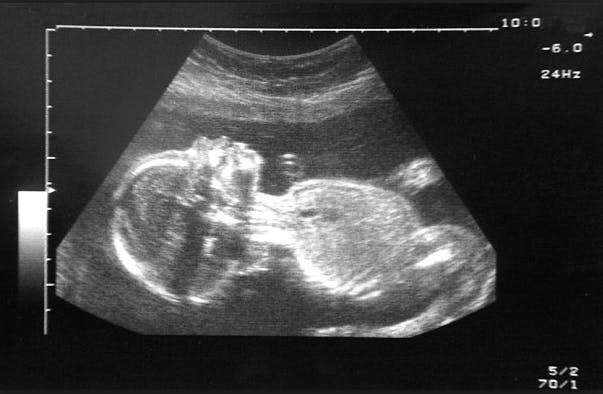

During an ultrasound the sonographer runs a plastic scanner over the mother’s naked belly, and that classic grainy image of the fetus appears on screen. For Anton, this was a romantic opportunity. The hottie held the mouse — ‘She is learning the ropes’ — Anton placed his mitt over hers and together their hands glided over my belly, circling, swooping in the manner of Torvill and Dean. ‘Spine, kidneys…’ Anton whispered lovingly in her right ear, ‘head circumference, abdomen, femur…’ Can we find out the baby’s gender? I asked. Is everything OK? Anton kept schtum. Why do some sonographers stay silent, when every parent they meet looks desperately to them for reassurance?

Anton had three reasons to support his theory. The first was a discrepancy between the baby’s head size (normal) and his stomach (small). The second was a relatively new test, the ‘doppler’ scan of uterine arteries. ‘High resistance,’ said Anton. ‘Baby struggling.’ The third reason was the most surreal: ‘Deep placental legs,’ said Anton. Legs? ‘Yes. Legs.’ Legs? I asked again, pointing to my own.

Anton’s eventual diagnosis, written like a death sentence across our scan notes, was: IUGR. Interuterine growth restriction (early onset). He did mention that only the fetal specialist could make a proper diagnosis, but the specialist wasn’t free for five days. Anton also made it plain he thought our child a write-off. ‘Do you still want to know the sex?’ he said as we fumbled silently into our coats. ‘Still’? Why ‘still’? I stared at him blankly. He shrugged. ‘Boy,’ he said and turned away.

Anton’s mistake, the professor explained, was false certainty. He’d doomed my baby on the basis of measurements he should have seen only as guidelines. ‘Your baby was upside down for the first scan. This means all the measurements get squashed,’ he said. ‘They are not to be trusted.’ Even if the baby had been right way up, the measurements and how they’re interpreted are approximate. The parameters for normality used in most NHS hospitals are based on studies from the 1970s.